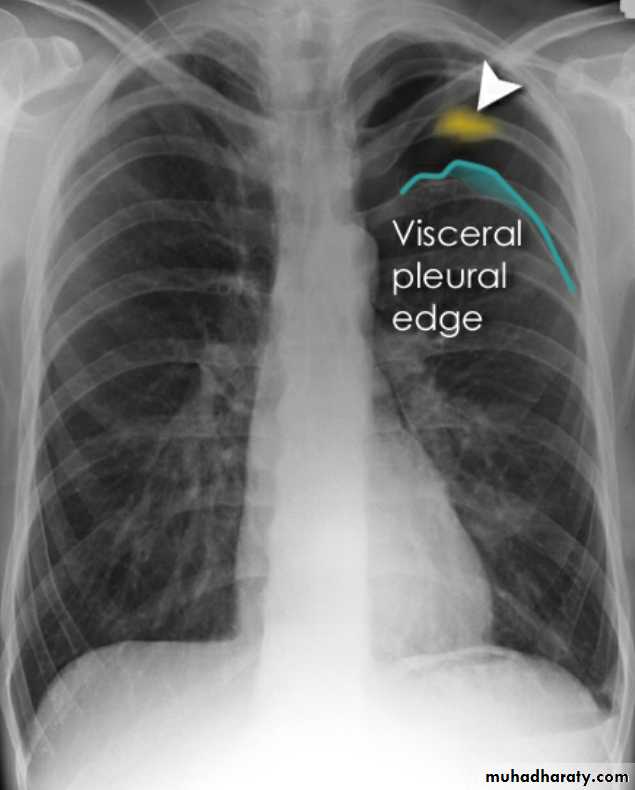

Pneumothorax

Pneumothorax refers to the presence of gas (air) in the pleural space. When this collection of gas is constantly enlarging with resulting compression of mediastinal structures it can be life-threatening and is known as a tension pneumothoraxIt is useful to divide pneumo thoraces into three categories :

Radiographic features

Chest radiographA pneumothorax is, when looked for, usually relatively easily appreciated. Typically they demonstrate:

visible visceral pleural edge see as a very thin, sharp white line

no lung markings are seen peripheral to this line

the peripheral space is radiolucent compared to adjacent lung

the lung may completely collapse

the mediastinum should not shift away from the pneumothorax unless a tension pneumothorax is present